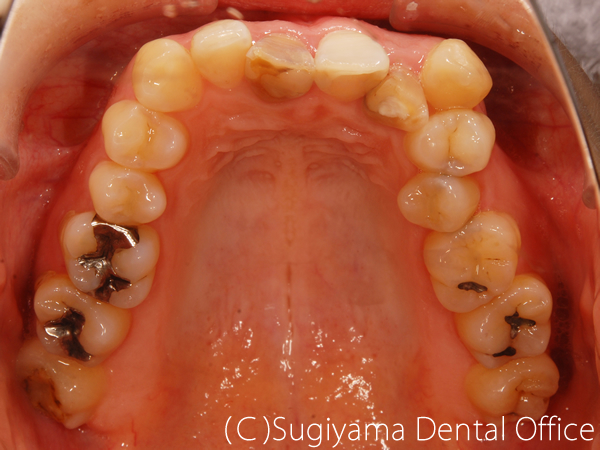

術前症例写真

術後症例写真

前歯を綺麗にしてほしいということで来院した女性の患者さんです。

親知らずは抜歯しましたが、そのほかは1本も歯を抜かずに矯正治療を仕上げました。

変色が著しかった前歯2本はオールセラミッククラウンで治しました。

歯が綺麗になったことで、笑顔がさらに美しくなりました。